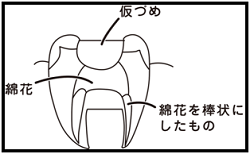

⑥ 前回詰めた綿花の状態を確認して、良い状態なら、「根管充填剤」(マスターポイント・アクセサリーポイント)というお薬を、余分な空間がないように根っこに詰めます。

⑥ 前回詰めた綿花の状態を確認して、良い状態なら、「根管充填剤」(マスターポイント・アクセサリーポイント)というお薬を、余分な空間がないように根っこに詰めます。 Q1.痛みはありますか?

⑤ 次に、仮詰めをします。

⑤ 次に、仮詰めをします。 虫歯が神経まで達して炎症を起こしているので、人によってはズキズキとした痛みを感じる方もいます(>_<)